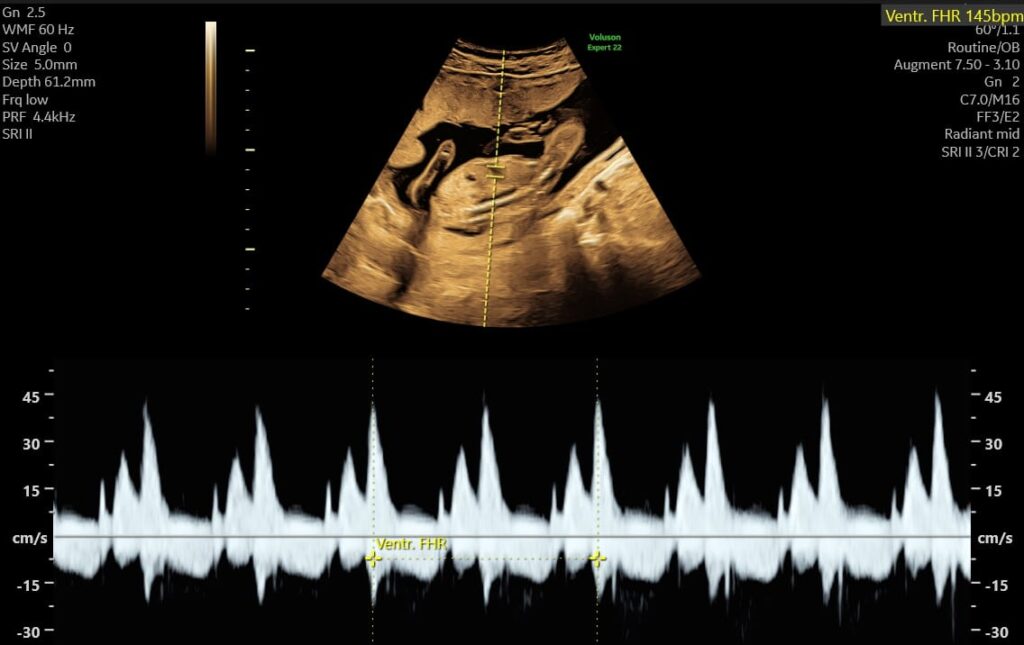

- hjerteaktivitet

Vi vurderer bl.a. hjerteaktivitet, bevægelse, fostervandsmængde, moderkagens placering og generelle trivselstegn.